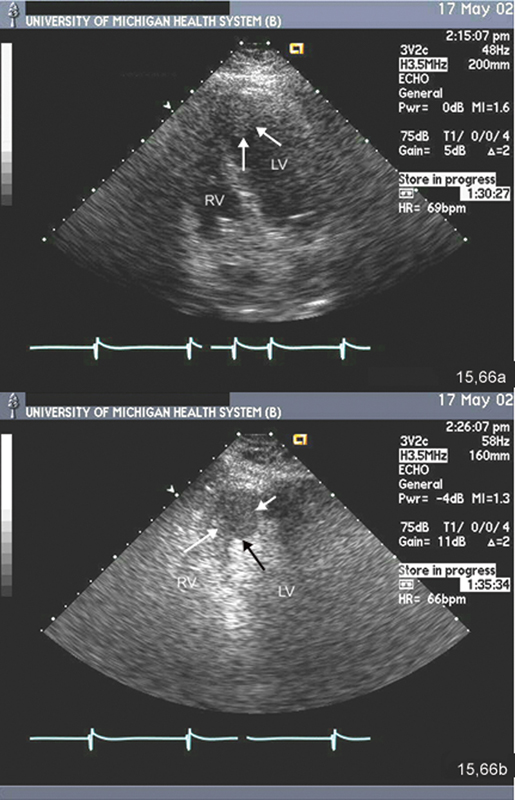

فحوصات تشخيصية لبعض امراض القلب والشرايين التاجية